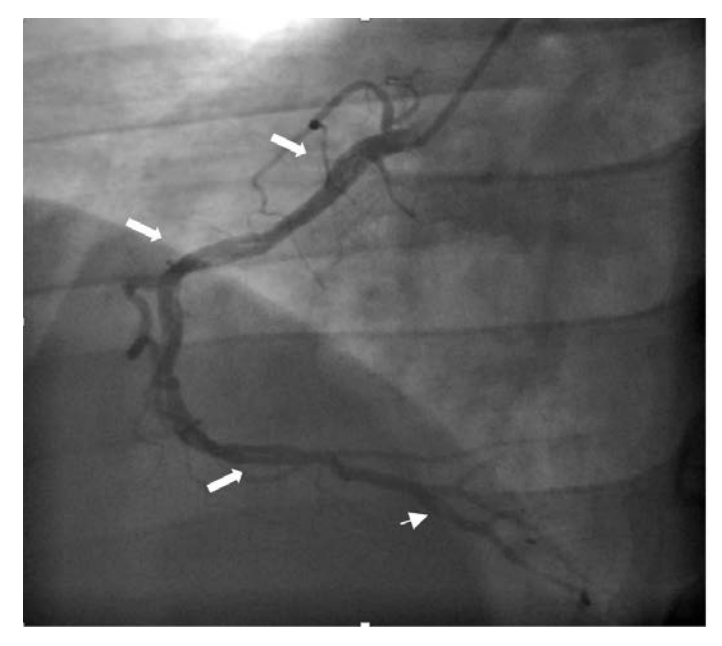

– A subsequent coronary angiogram revealed diffuse organized filling defects with TIMI III flow of obtuse marginal artery (OM) and right coronary artery (RCA) consistent with chronic thromboembolism of coronary arteries.